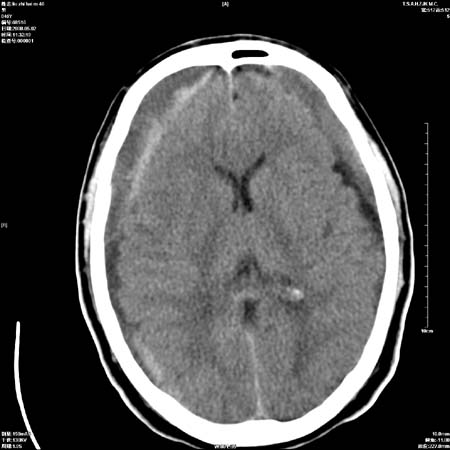

男性   46岁   头晕头痛一周    无任何外伤史    有高血压病史

亚急性硬膜下血肿

考虑双侧慢性硬膜下出血

支持双侧慢性硬膜下血肿。

应该是亚急性(3天——3周)硬膜下出血

亚急性硬膜下血肿;典型。